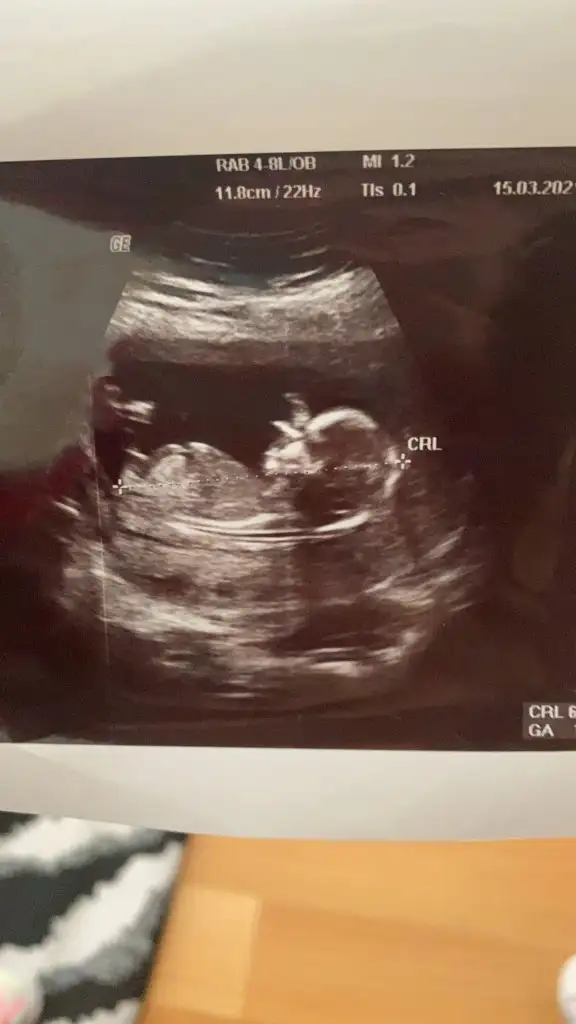

12+3 haftalik benim bebegimide yorumlar misin?Ikra meyra

Alttaki bacak arasi görüntüsü

doktorum 1 ay sonra söylerim dedi merak ediyorum.. :)

videodan ss aldim